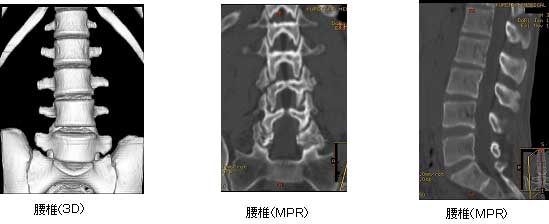

当クリニックでは、最新型の16列全身用コンピュータ断層撮影装置 Revolution ACTを使用しています。

CT 検査による画像例